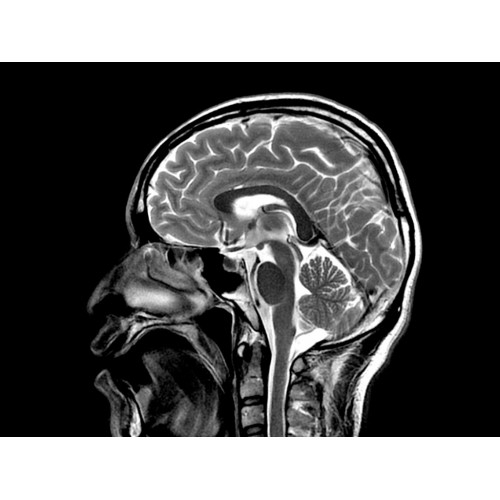

МР-томограф Optima MR450w позволяет получать изображения исключительно высокого качества, которые помогают установить диагноз. Чтобы удовлетворить ожидания клиентов в отношении высокого качества, в МР-томографе Optima MR450w были сохранены дополнительные возможности платформы Discoverу, привнесшие в его работу универсальность и мощь.

• Магнит переработанной конструкции — полностью новый магнит длиной 145 см обеспечивает однородную контрастность тканей в удобных для пациента условиях.

• Градиентная подсистема eXtreme — мощная градиентная подсистема для исследования тела характеризуется градиентом 34 мТл/м и скоростью нарастания градиента 150 Тл/м/с по каждой оси, что обусловливает быстроту, точность и высокую воспроизводимость сканирования.

• Цифровой РЧ-приемник OpTix — эксклюзивная оптическая РЧ-система увеличивает четкость сигнала и его интенсивность, формируя чистые и резкие изображения.

• РЧ-катушки, оптимизированные для исследования конкретных участков тела — элементы катушек высокой плотности располагаются вокруг исследуемых участков тела и при необходимости обеспечивают расширенный охват и оптимальное качество изображений при каждой процедуре.